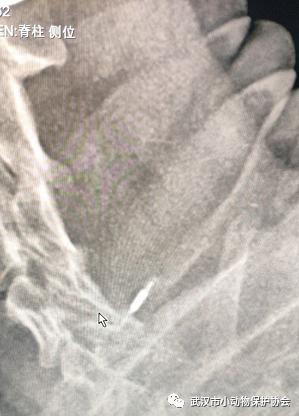

医生立刻给它做了检查

就在我们都为它的结果担心的时候

噩耗也随之而来

狗狗的肿瘤是恶性的

并且已经扩散到了肺部

医生还从狗狗身体里检查出了另外一个东西

——

芯片